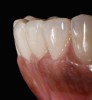

A patient in her 60s wanted to improve her smile but declined orthodontic treatment in favor of porcelain veneers (Figure 13). However, addressing her 8-mm pocket was the first step. The practitioner created biologically clean root surfaces using ultrasonic open-flap debridement, finishing burs, and manual tool instrumentation. Next, a mineralized freeze-dried bone allograft saturated in platelet-derived growth factor (Figure 14) using chemotaxis pulled the stem cells capable of regeneration into the site where repopulation was needed. Prior to closure, a resorbable membrane, polylactic acid-guided tissue regeneration—known for periodontal regeneration—was used (Figure 15). At 10 weeks, adequate healing had occurred. The patient at 6 and 10 weeks showed continued healing. Although some postoperative recession was evident, probing depths were less than 2 mm, and the patient was referred back to the restorative dentist for restorative therapy. As of this writing, she has not lost any teeth and is periodontally stable (Figure 16).

The pretreatment situation.

Figure 13